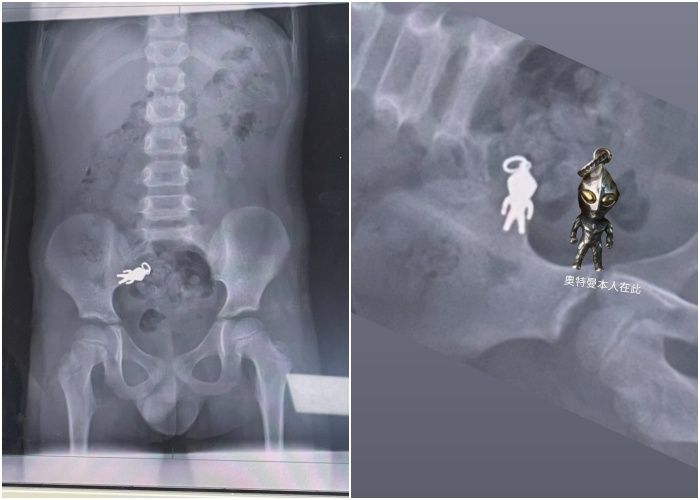

▲男童誤吞「吊飾」,家人鬆一口氣:超人任務完成。(圖/網友shushu1011授權,下同)

原PO將X光片分享到Threads,照片中清楚可見吊飾完整輪廓,並幽默標註「奧特曼(超人力霸王)本人在此」(如下圖),引起網友熱烈討論,留言笑翻:「這X光片能拿去裱框嗎?」、「已快走到出口了」等。

羅東博愛醫院小兒科醫師謝錦桐表示,吊飾大小約2.8公分×1.4公分,已隨腸道蠕動到小腸,男童身體狀況良好,暫不需手術,只要在家持續觀察,有機會自行排出。其他醫師也提醒,如果出現劇烈腹痛、嘔吐或長時間無法排便等症狀,需立即就醫;若孩子精神活潑、正常進食活動,則可繼續觀察。